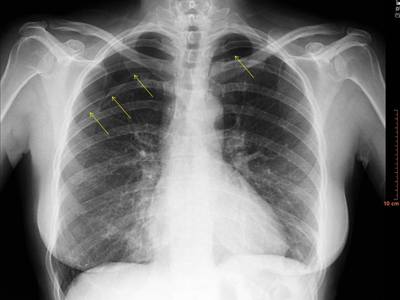

Figura 1: Radiografía de tórax con neumotórax en ápex derecho de aproximadamente un 25% de extensión y neumotórax en fosa supraclavicular izquierda (flechas).